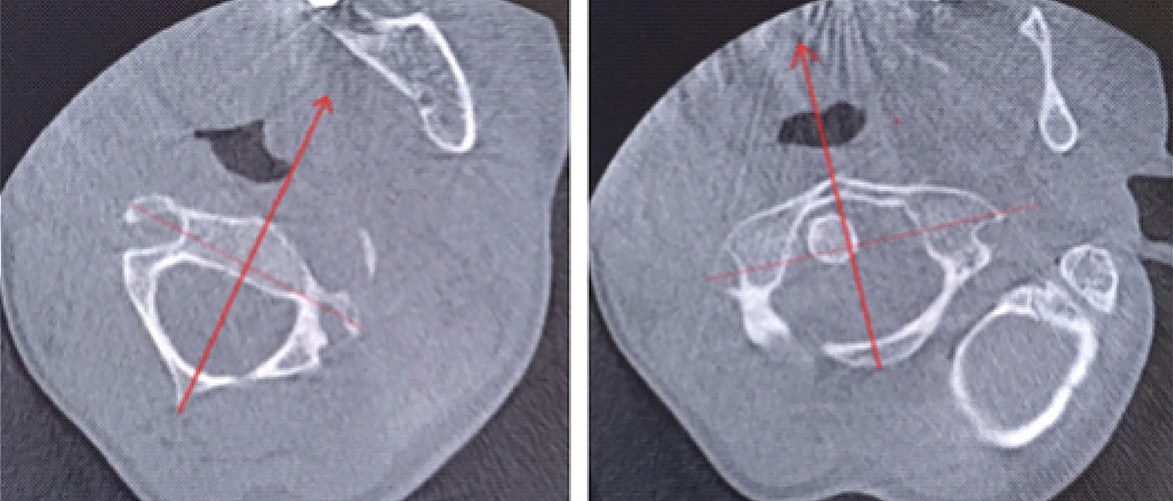

Для уточнения характера выявленных изменений в ручном режиме с помощью программы Adobe Photoshop© выполнено наложение аксиальных срезов 1-го и 2-го шейных позвонков, полученных по отдельности, с созданием единого изображения с возможностью комплексной оценки взаимоотношений изучаемых сегментов (рис. 2). При анализе смоделированного изображения обнаружено, что ротация атланта составляет 35° вправо (рис. 3). Суставные поверхности латерального атлантоаксиального сустава справа совпадают, а слева –суставная поверхность атланта смещена кпереди, что соответствует ротационному подвывиху типа II по классификации J. W. Fielding и R. J. Hawkins [8].

Рис. 2. Конусно-лучевая компьютерная томография краниовертебральной области. Аксиальные срезы на уровне аксиса (А) и на уровне атланта (Б). Стрелками обозначены передне-задние оси позвонков